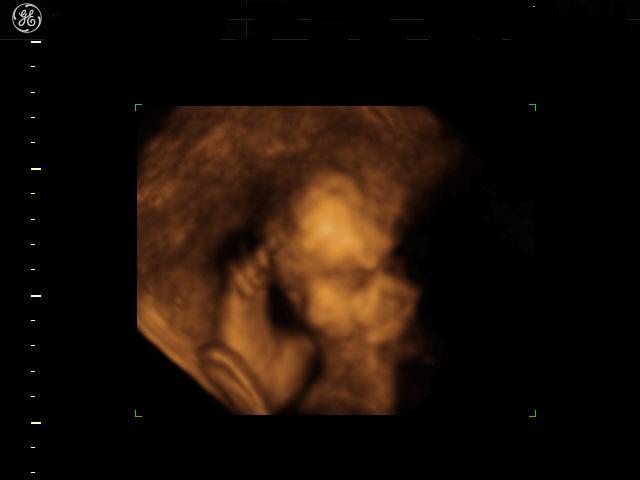

We went for our 3D/4D Sono and found out we're having a

BOY !!!

We are so excited! We had such a great experience. If you have the means to do it I would reccomend it to anyone. The tech was so nice and knowledgeable and patient. The baby did not want his picture taken at all. They were so good about it that they gave us a complimentary scan. FM for more info if you'd like.

So I would like to introduce you to our son, Josh Jr.